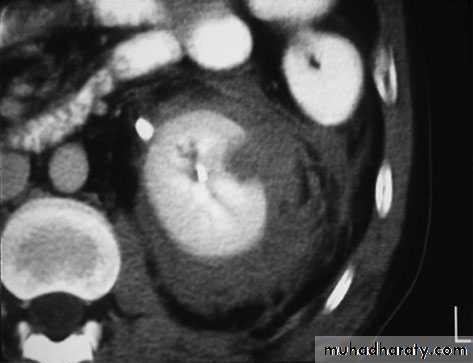

deep central renal laceration and large perirenal hematoma with intravascular contrast extravasation

Treatment

Nephrectomt:::::For severe renal injuries producing life-threatening bleeding, prompt nephrectomy is warranted.

These are usually unstable patients who persist in shock despite multiple transfusions and have deep renal lacerations near the hilum